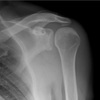

What imaging modality is primarily used for diagnosing shoulder dislocation?

A

Plain radiograph

This will reveal the displacement of the humeral head.

Which X ray views to do for shoulder dislocation?

AP view + Y or axilliary view BOTH before & after reduction

What is a key sign for posterior shoulder dislocation?

Lightbulb sign